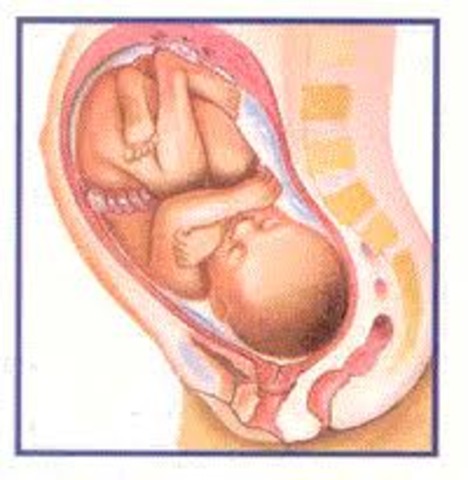

• week 37

week 37

Baby weighs close to 2.8kg and about 48.6cm long from head to toe. Head cradled in pelvic cavity. Surrounded and protected by pelvic bones. Full head of hair, with locks up to 3.5cm long. Downy coat of lanugo that covered the baby from week 26 has disappeared. Also, so has the vernix caseosa, the protective whitish substance that also covered the baby